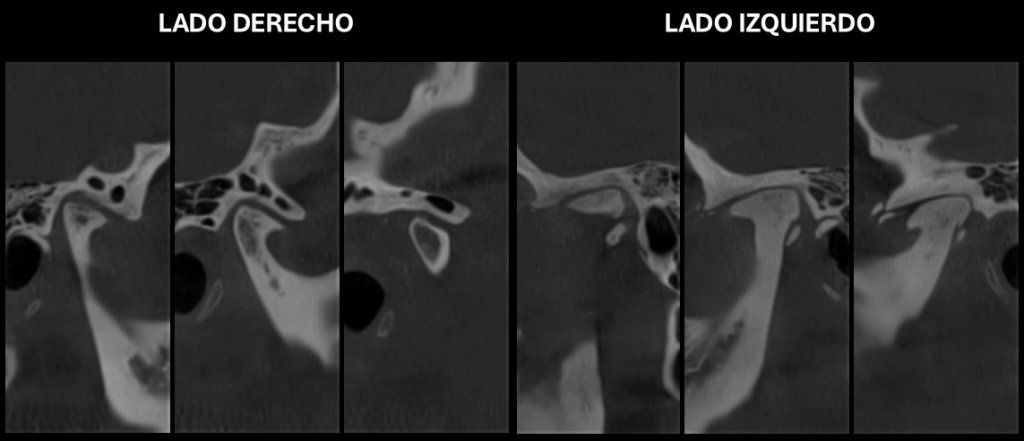

En la ampliación imagenológica con tomografía computarizada de haz cónico se identifica en el lado derecho se aprecia aplanamiento y esclerosis de la cabeza condilar, con formación de osteofito, presencia de pseudoquiste subcondral y erosión en el contorno superior, además de una disminución del espacio articular en las regiones posterior y lateral. En el lado izquierdo se observa aplanamiento y esclerosis que comprometen la cabeza y el cuello condilar, con osteofito asociado y múltiples cuerpos óseos libres alrededor del cóndilo. Asimismo, se identifica una reducción del espacio articular en las regiones posterior, superior, medial y lateral.

Cortes Coronales Oblicuos